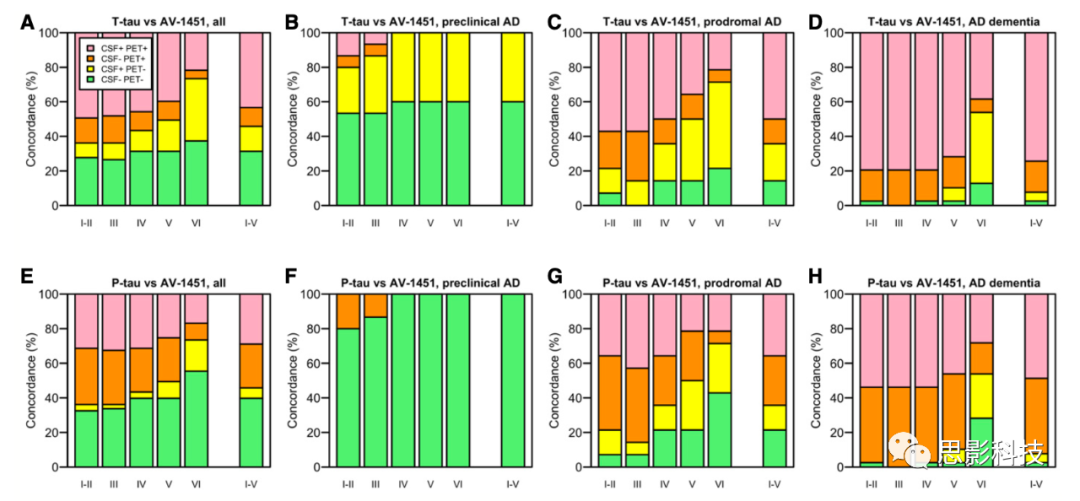

5、EMBO Molecular Medicine:18F-AV-1451 、CSF T-tau 和 P-tau 可作为阿尔兹海默的生物标志

Tau病理学是阿尔兹海默的关键特征,但是脑脊液tau和tau PET测量的关系尚不清楚。为了阐明阿尔茨海默中脑脊液(CSF)总tau(total-tau,T-tau)、磷酸化tau(phosphorylated tau,P-tau)与tau PET受体18F-AV-1451之间的关系,研究者检查了30名认知健康的老年人(包含15名临床前AD),14名潜伏期AD和39名AD痴呆患者。通过腰椎穿刺获取脑脊液,同时采集MRI结构像和18F-AV-1451 PET。利用皮尔逊相关、线性回归模型等计算各指标间的关系。

结果发现:

(1)CSF T-tau和P-tau高度相关(R = 0.92,P <0.001),但它们与18F-AV-1451仅中等程度相关,且主要表现在AD痴呆患者中,潜伏期AD很少相关,对照组不存在显著相关。

(2) 18F-AV-1451与大脑萎缩和认知障碍密切相关,而CSF tau 仅与神经退行性变轻微相关,与认知障碍无相关。

(3)对于临床前AD,CSF tau会显著升高而18F-AV-1451保持正常。但是对于痴呆患者,疾病阶段18F-AV-1451会升高,CSF tau有的升高有的不升高。

因此得出结论:脑脊液T-tau和P-tau主要表现为“疾病状态”的生物标志,因为对于很多AD病例中,在所有疾病阶段,它们似乎都增加了。相反,18F-AV-1451是“疾病阶段”的生物标志,因为它在疾病的临床阶段会增加,并与脑萎缩和认知能力下降有关。

原文:18F-AV-1451 and CSF T-tau and P-tau as biomarkers in Alzheimer’s disease

DOI:10.15252/emmm.201707809